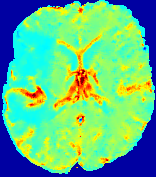

LesionRefer to captionRefer to captionRefer to captionRefer to captionRefer to captionRefer to caption𝐕rgbsubscript𝐕𝑟𝑔𝑏{\bf{V}}_{rgb}Refer to captionRefer to captionRefer to captionRefer to captionRefer to captionRefer to caption𝐕2subscriptnorm𝐕2{\|\bf{V}}\|_{2}Refer to captionRefer to captionRefer to captionRefer to captionRefer to captionRefer to captionRefer to caption3.53.53.52.82.82.82.12.12.11.41.41.40.70.70.70.00.00.0(mm/s)𝑚𝑚𝑠(mm/s)D𝐷DRefer to captionRefer to captionRefer to captionRefer to captionRefer to captionRefer to captionRefer to caption0.0200.0200.0200.0160.0160.0160.0120.0120.0120.0080.0080.0080.0040.0040.0040.0000.0000.000(mm2/s)𝑚superscript𝑚2𝑠(mm^{2}/s)Slice #1Slice #2Slice #3Slice #4Slice #5Slice #6

Figure 4: PIANO feature maps for another patient in the ISLES 2017 training set, where the lesion is located in the right hemisphere. Top row: segmented stroke lesion region (white) on different slices. The corresponding slices for the PIANO feature maps are shown in the following rows.

For a better insight into an estimated velocity field 𝐕𝐕{\bf{V}} and diffusion field 𝐃𝐃{\bf{D}}, we compute the following maps: (1) 𝐕rgbsubscript𝐕𝑟𝑔𝑏{\bf{V}}_{rgb}: Color-coded orientation map of 𝐕=(Vx,Vy,Vz)T𝐕superscriptsuperscript𝑉𝑥superscript𝑉𝑦superscript𝑉𝑧𝑇{\bf{V}}=(V^{x},V^{y},V^{z})^{T}, obtained by normalizing 𝐕𝐕{\bf{V}} to unit length and mapping its 3 components to red, green, blue respectively; (2) 𝐕2subscriptnorm𝐕2\|{\bf{V}}\|_{2}: 222 norm of 𝐕𝐕{\bf{V}}; (3) D𝐷D: scalar field in Eq. 5.

Fig. 3 and Fig. 4 show the PIANO feature maps estimated from two ISLES 2017 patients: all are highly consistent with the lesion in both cases. Details of the blood flow trajectories are revealed in 𝐕rgbsubscript𝐕𝑟𝑔𝑏{\bf{V}}_{rgb} by the ridged patterns and the sharp changes of colors in the unaffected (right) hemisphere, while the flat patterns appearing within the lesion provide little directional information about the velocity and indicate low velocity magnitudes. Velocity magnitudes are more directly visualized via 𝐕2subscriptnorm𝐕2\|{\bf{V}}\|_{2}, from which one can easily locate the lesion where 𝐕2subscriptnorm𝐕2\|{\bf{V}}\|_{2} is low. D𝐷D also indicates lower diffusion values in the lesion, though with less contrast potentially due to the fact that it captures the accumulated effect of CA diffusion at the voxel-level.